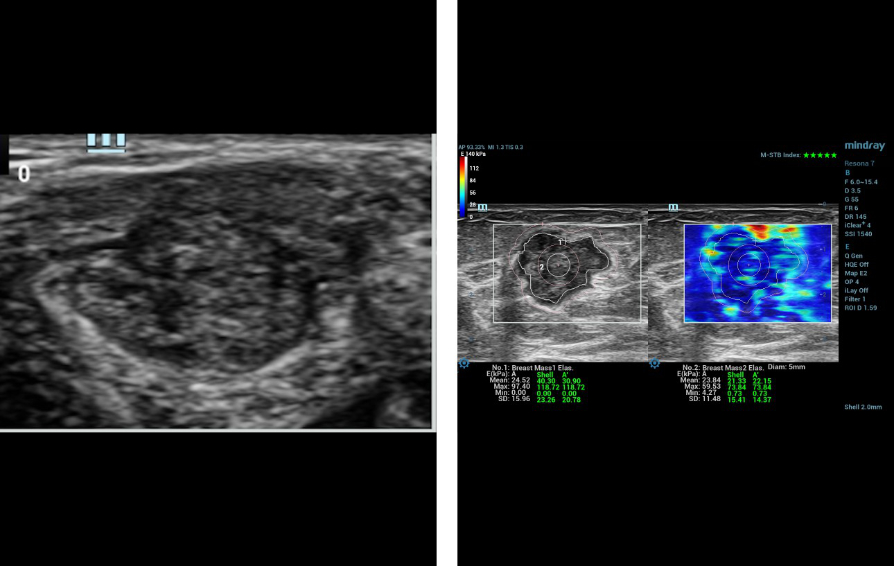

Case Report 1

57-year-old female, patient A presented with a left breast lump of 6 months duration. There was a lump measuring 19x15mm in size at the 2 OŌĆÖclock position of the left breast. B-mode ultrasound categorized this lesion as BIRADS 5. Before performing the biopsy, the patient underwent shear wave elastography (SWE) using L14-3WU (bandwidth frequency = 3.8-15.4 MHz, FOV-50.8mm) linear array transducer of Resona 7 diagnostic ultrasound system by Mindray Medical International, Shenzhen, China.

- The ratio of the lesion to normal breast tissue SWE values

The Maximum and mean values in the selected ROI manually along the edge of the lesion are 97.4 kPa and 24.5 kPa. The maximum value in the 2mm shell around the lesion is 118.7 kPa. The maximum and mean values in the lesion + shell are 118.7 kPa and 30.9kPa. Maximum and minimum values in the center of the lesion with a circular ROI measuring 5mm in diameter are 59.5kPa and 23.8kPa.